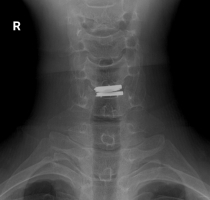

手术由罗肖主任团队精准实施。术中,团队在毫米级的操作空间内,完美避开了毗邻的脊髓、神经根和血管,成功置入了人工颈椎间盘假体。术后影像显示,假体位置精准,神经压迫完全解除。患者恢复迅速,术后第二日上肢症状即显著缓解,且能在保护下早期开始颈部功能活动,对治疗效果非常满意。

术后DR提示假体位置良好